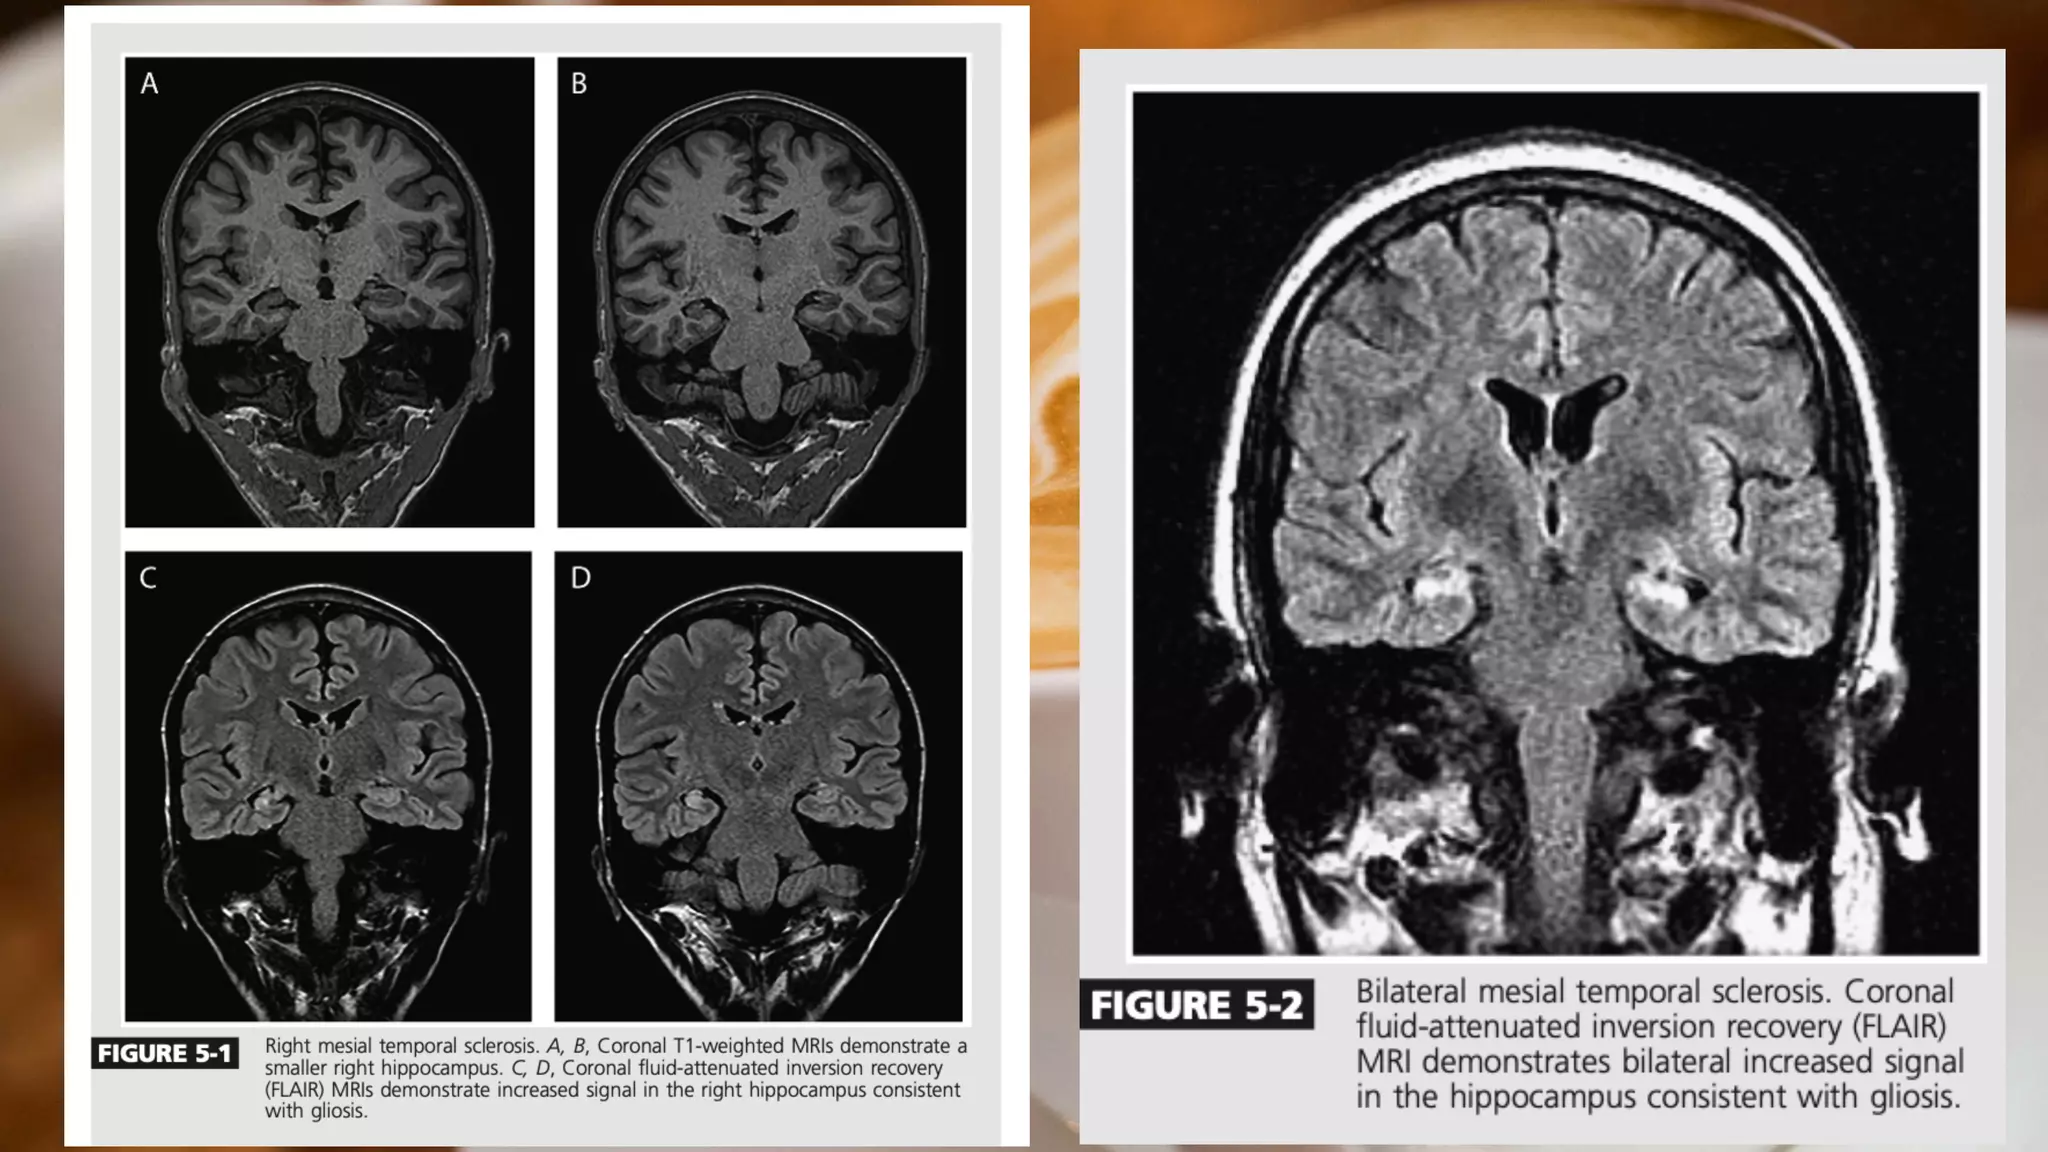

Prolonged febrile seizures believed to be risk factor for development of hippocampal sclerosis(a

common cause of mesial temporal lobe epilepsy)

Hippocompal sclerosis is characterised by atrophy and gliosis of the hippocampus (unilateral or

bilateral)

Other aetiologies of mesial temporal lobe epilepsy ie cavernous

hemangiomas,gliosis,encephalomalacia secondary to prior injury and tumour ie dysembroplasric

neuroepithelial tumours

Imaging

Key imaging characteristics to evaluate for hippocampal

sclerosis are asymmetric size (smaller on the affected side) and

increased T2 signal in the hippocampus consistent with gliosis.

Mesial Temporal lobeepilepsy Often begins during late adolescence or early adulthood Prolonged febrile seizures believed to be risk factor for development of hippocampal sclerosis(a common cause of mesial temporal lobe epilepsy) Hippocompal sclerosis is characterised by atrophy and gliosis of the hippocampus (unilateral or bilateral) Other aetiologies of mesial temporal lobe epilepsy ie cavernous hemangiomas,gliosis,encephalomalacia secondary to prior injury and tumour ie dysembroplasric neuroepithelial tumours

Imaging An MRI ofthe brain without contrast is recommended in the evaluation of a patient with suspected mesial temporal lobe epilepsy . An enhanced MRI may be used dependent on local imaging protocols and suspected etiologies. It is preferable to include coronal T1- and T2-weighted images with thin cuts (less than 3 mm) through the temporal lobes to properly evaluate the hippocampus.

• 26.

Imaging Key imaging characteristicsto evaluate for hippocampal sclerosis are asymmetric size (smaller on the affected side) and increased T2 signal in the hippocampus consistent with gliosis. Inclusion of gradient echo imaging may assist in the identi fi cation of vascular etiologies